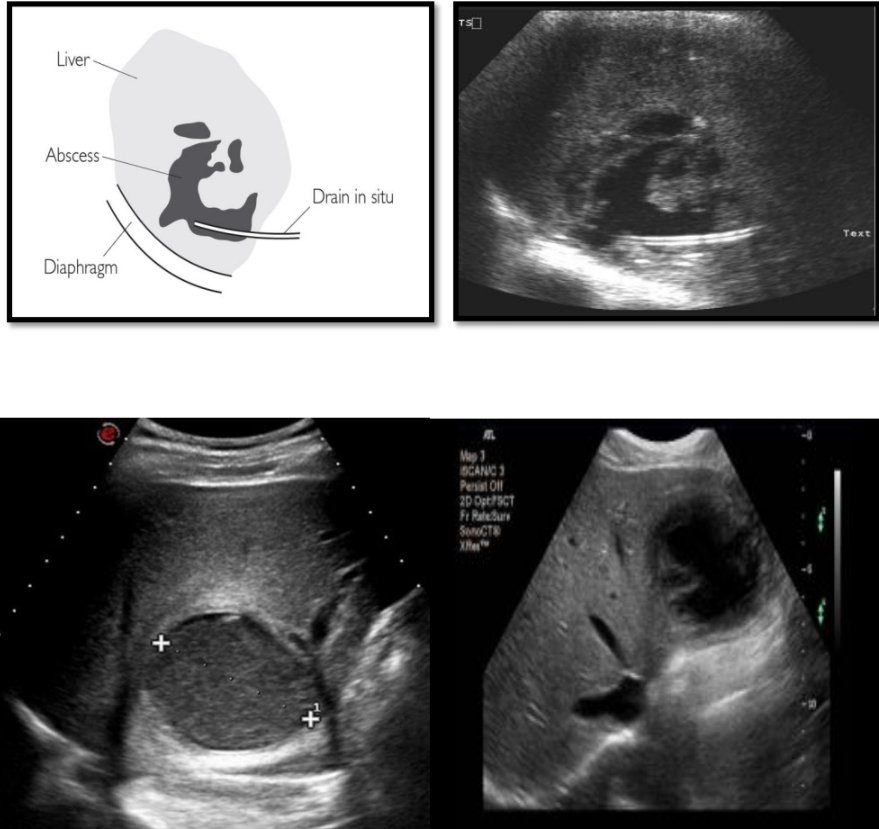

Liver abscess  Thick wall with Irregular margin  Contain ‘lumpy’ echo-bright debris (turbid content)  Display variable postacoustic enhancement  If the abscess contains gas intense reverberations are seen. #ultrasound #sonologist

Liver abscess

 Thick wall with Irregular margin

 Contain ‘lumpy’ echo-bright debris (turbid content)

 Display variable postacoustic enhancement

 If the abscess contains gas intense reverberations are seen.

#ultrasound

#sonologist